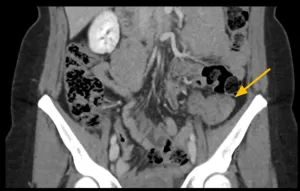

Fase nefrográfica

Fase excretora

Imagens-chave

Derivação urinária em alça delgada na fossa ilíaca à esquerda. Houve boa distensão da alça de derivação, porém nota-se falha de enchimento de aspecto polipoide na fase excretora medindo cerca de 2,2 x 1,0 cm. Sugere-se prosseguir investigação.

• Lesão polipoide na alça ileal da derivação urinária